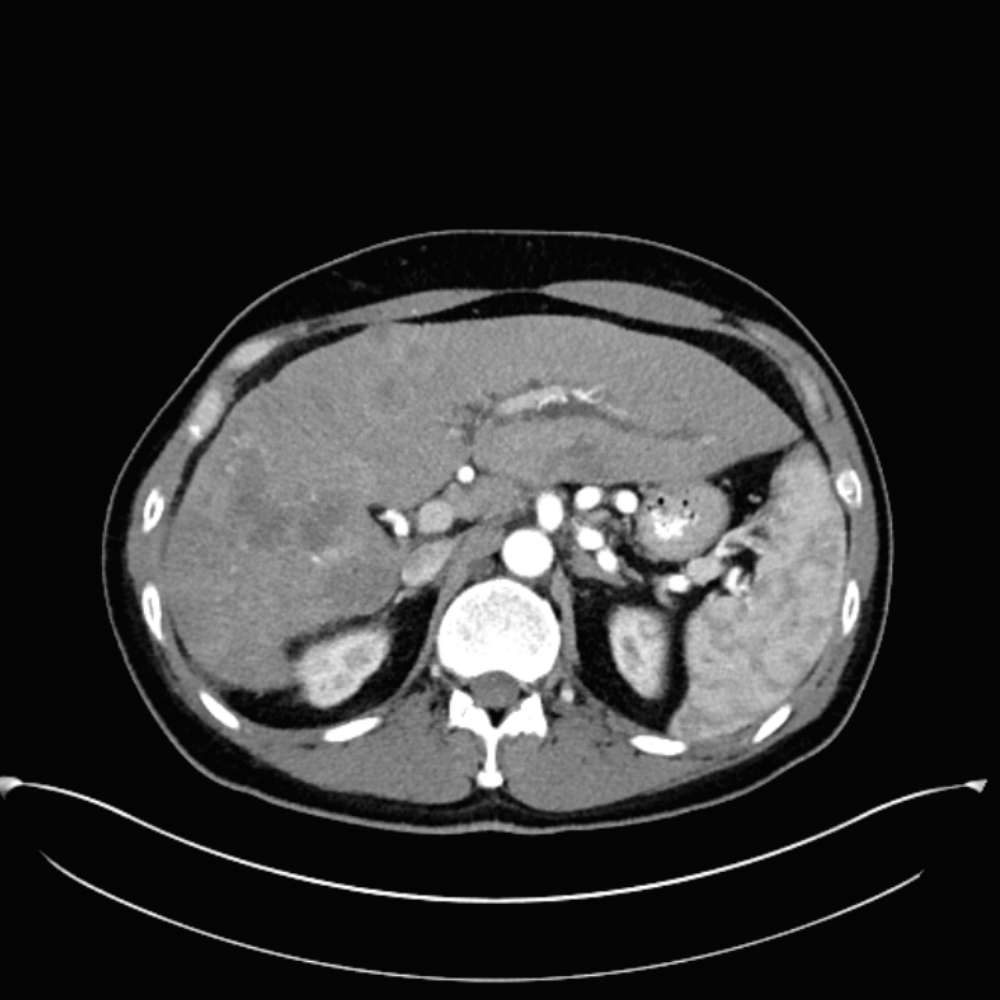

Case study

1. Targeted cannulation of a single enlarged segmental branch in the left lobe of the liver in cases of liver metastases.

Case 1